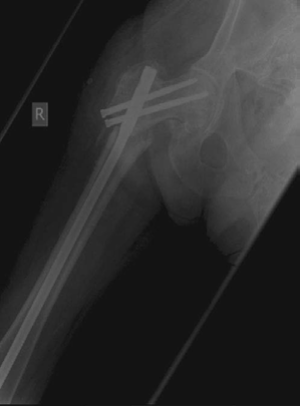

Minute 4 EXAMINER : You fixed it with this recon nail. What do you think about your check X-ray? (Figure 8.12.) CANDIDATE : As I mentioned earlier the literature reports better results with the use of a cephalomedullary nail. I hope that when the recon nailing was performed bone grafting to the fracture site was performed as well so as to address both biomechanics and biology. The cephalomedullary nail is in slight varus and there is some translation at the fracture site. The screws in the proximal fragment are a bit superior to where I would normally like them. The screws are not absolutely parallel and I would study my lateral radiographs carefully to make sure that the screws have not missed the head.